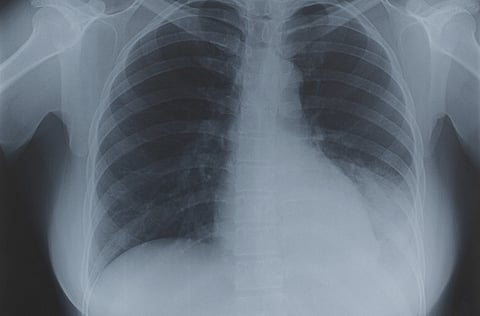

When the researchers deleted the gene for LRRK2 in mice, they found that they exhibited an enhanced early immune response to TB infection, and had significantly lower levels of Mtb in their lungs than control mice up to two weeks after infection.